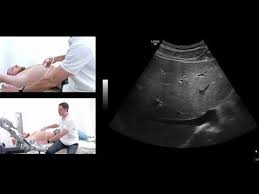

Kidney Ka Ultrasound Kaise Hota Hai

Scan aur ultrasound kya alag hota hai. Jo silent kidney stone hotey h matlb ki jo pain ya harm nhi kartey unka pata to x rays se lagta h. Kidney ke andar patthar kis karan se hota hai. Scan aur ultrasound kya alag hota hai.